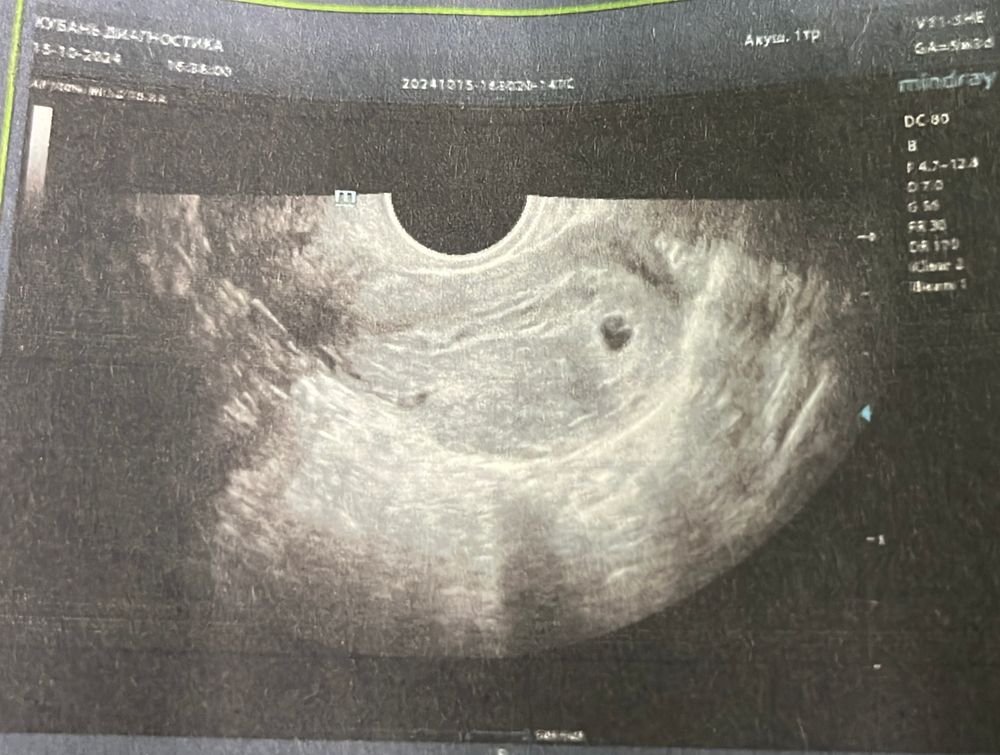

Окс, мне на первом узи поставили гематому,моя ре по снимку опровергла, на двух других узи гематомы нет… у вас есть снимок?

квитка, Изображение

Окс, вот эта ячейка? Изображение

квитка, нет, над плодным яйцом, длинная расплывчатая линия

Окс, на мое скромное мнение это не гематома… у меня так выглядят сосудистые синусы…переделаете узи у хорошего спеца через время и напишите,права я или нет 😀ну и в инете посмотрите как гематомы выглядят, там такое чёрное пятно как плодное яйцо,прям под плодным яйцо и как карман…